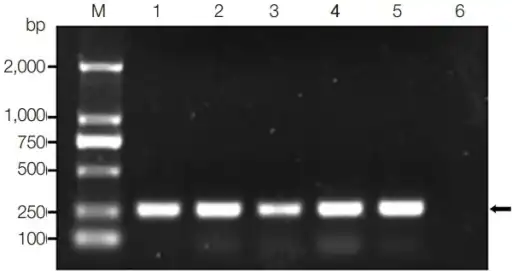

Infection is detected mainly on identification of eggs by microscopic demonstration in faeces or in duodenal aspirate, but other sophisticated methods have been developed, such as ELISA, which has become the most important clinical technique. Diagnosis by detecting DNAs from eggs in faeces are also developed using PCR, real-time PCR, and loop-mediated isothermal amplification, which are highly sensitive and specific.